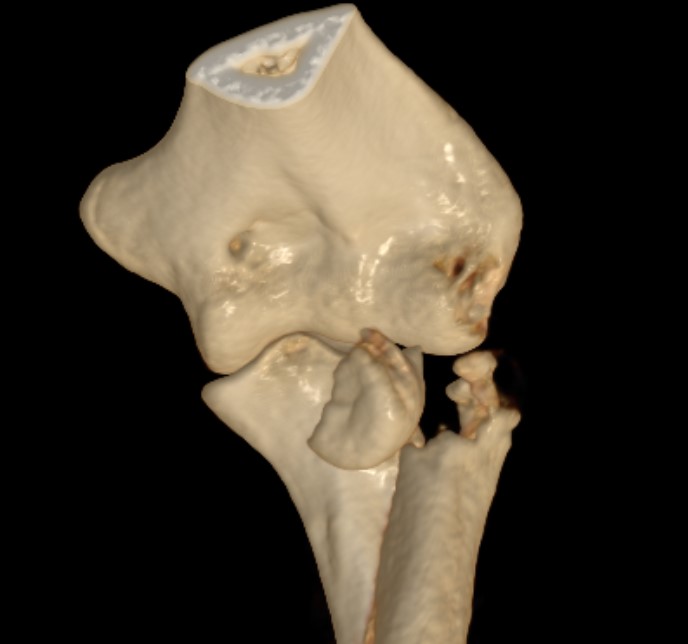

Overstuffing

| Lesser sigmoid notch | Symmetry of ulnohumeral joint |

|---|---|

|

Radial head shoulder articulate with lesser notch

Ensure no gapping of lateral ulnohumeral joint |

- cadaveric study

- increased medial ulno-humeral joint line gapping with overlengthening of 6 or 8 mm

- increased lateral ulno-humeral joint line gapping with overlengthening of 2 mm